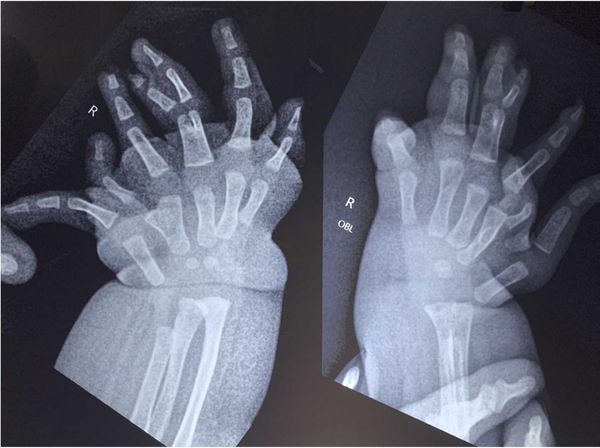

detikSumutRabu, 01 Okt 2025 11:30 WIB Bayi di India Lahir dengan Banyak Jari Tangan, Ini Penampakannya Anak berusia dua tahun lahir dengan kondisi langka. Saat lahir bayi tersebut memiliki banyak jari dan tulang lengan.